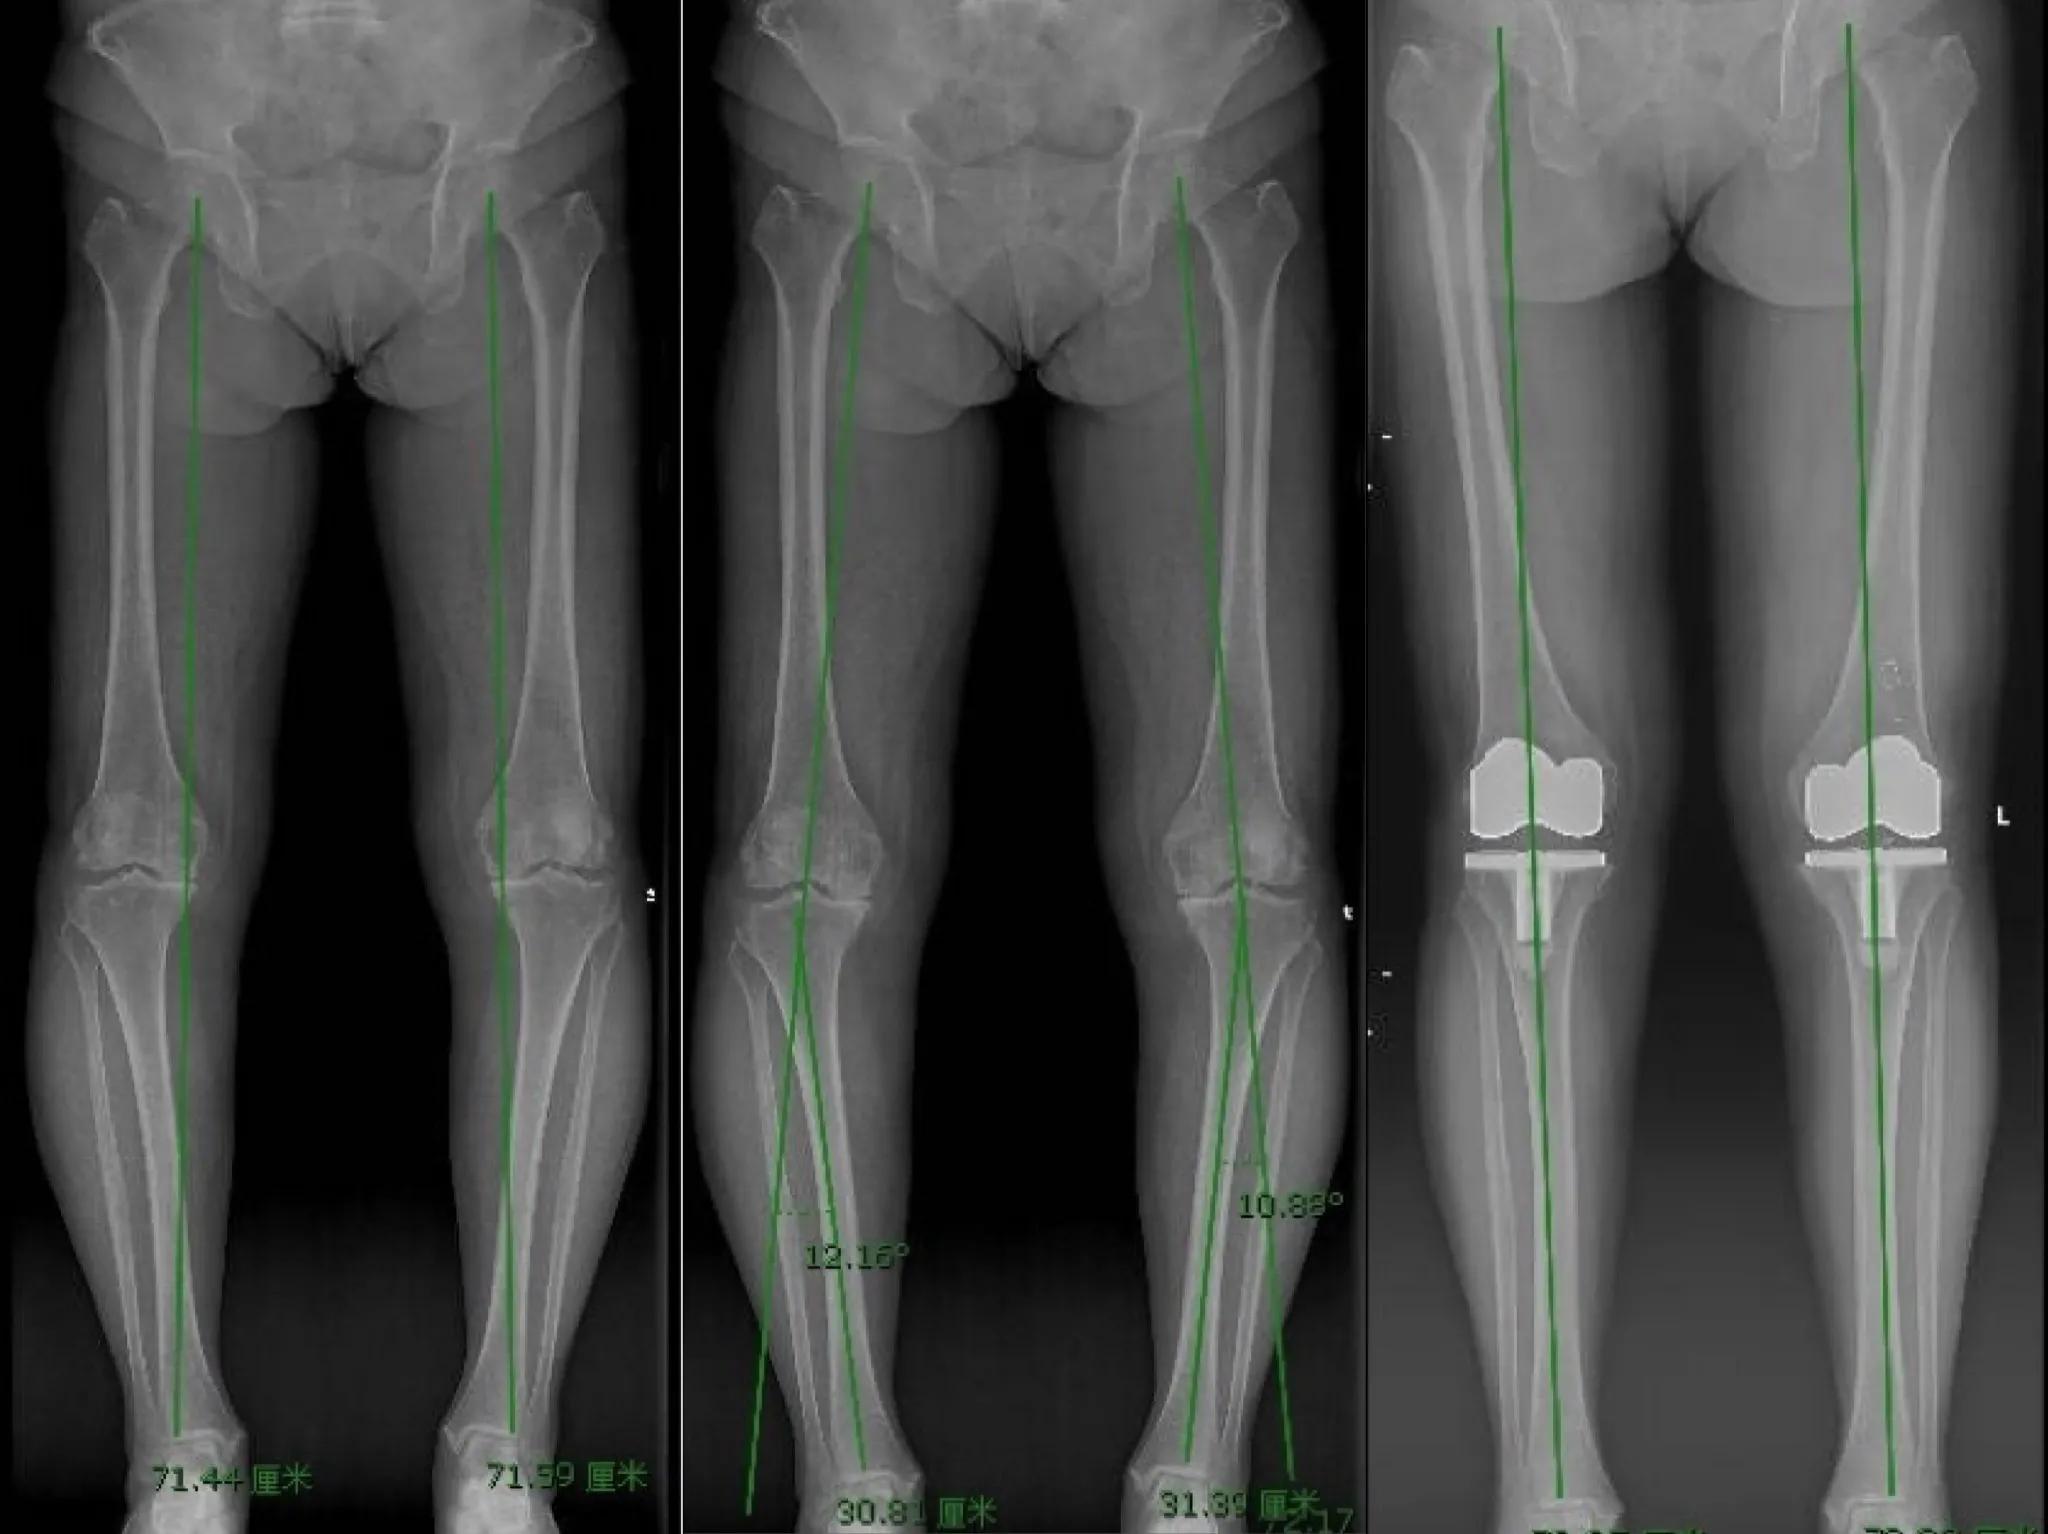

病例三:患者女性,68岁,双膝关节负重时疼痛5年余。查体:双膝关节屈曲内翻畸形,膝关节广泛压痛,膝关节ROM:左侧伸15°—屈110°,右侧伸10°—屈110°,双膝关节被动屈伸活动均可扪及摩擦感,双侧髌骨研磨试验(+),双下肢全长负重位X线片示左膝关节内翻11°,右膝12°,内侧关节间隙均消失。

该患者病史较长,呈典型全关节骨关节炎表现,伴固定屈曲内翻畸形。患者身体一般状况良好,本人及家属均有缓解疼痛、纠正畸形、提高生活质量的愿望。因此,本病例选择全膝关节表面置换术(Total Knee Arthroplasty, TKA)治疗,手术选择后稳定型假体,清理骨赘和炎性滑膜,恢复关节面的友好关系,重建双下肢正常力线。术后双下肢全长负重位X线片示双下肢力线通过膝关节中心。